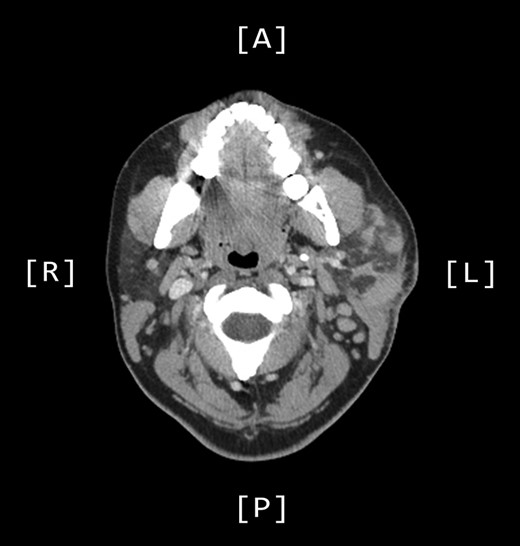

A positron emission tomography (PET) scan was subsequently arranged, which demonstrated increased uptake of the left parotid gland and several enlarged lymph nodes in the neck bilaterally (Figs 1 and 2).

Axial PET scans (A and B) showing increased uptake of the left parotid gland and enlarged left-sided lymph nodes in the neck.

A computed tomography (CT) scan demonstrated left parotid multifocal soft tissue abnormality and enlarged left-sided cervical lymph nodes, with prominent superficial left supraclavicular fossa lymph nodes (Figs 3 and 4).

Axial CT sinuses (with contrast) showing left parotid multifocal soft tissue abnormality and enlarged left-sided cervical lymph nodes.